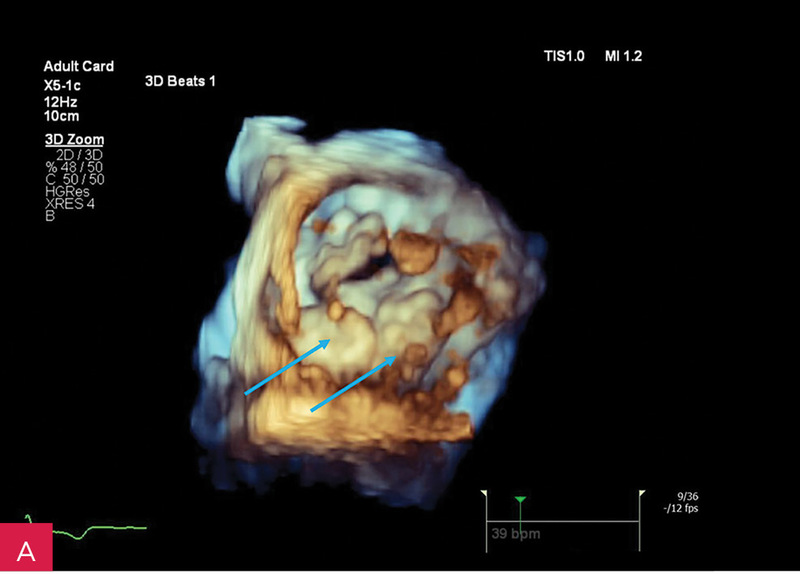

Rycina 4A, B. Badanie echokardiograficzne przezklatkowe trójwymiarowe (3D TTE) – widok od strony lewej komory zastawki mitralnej i guzowatej zmiany o nierównej powierzchni (A) wraz z prezentacją zmiany w przekrojach wykonanych na podstawie 3D TTE (B)